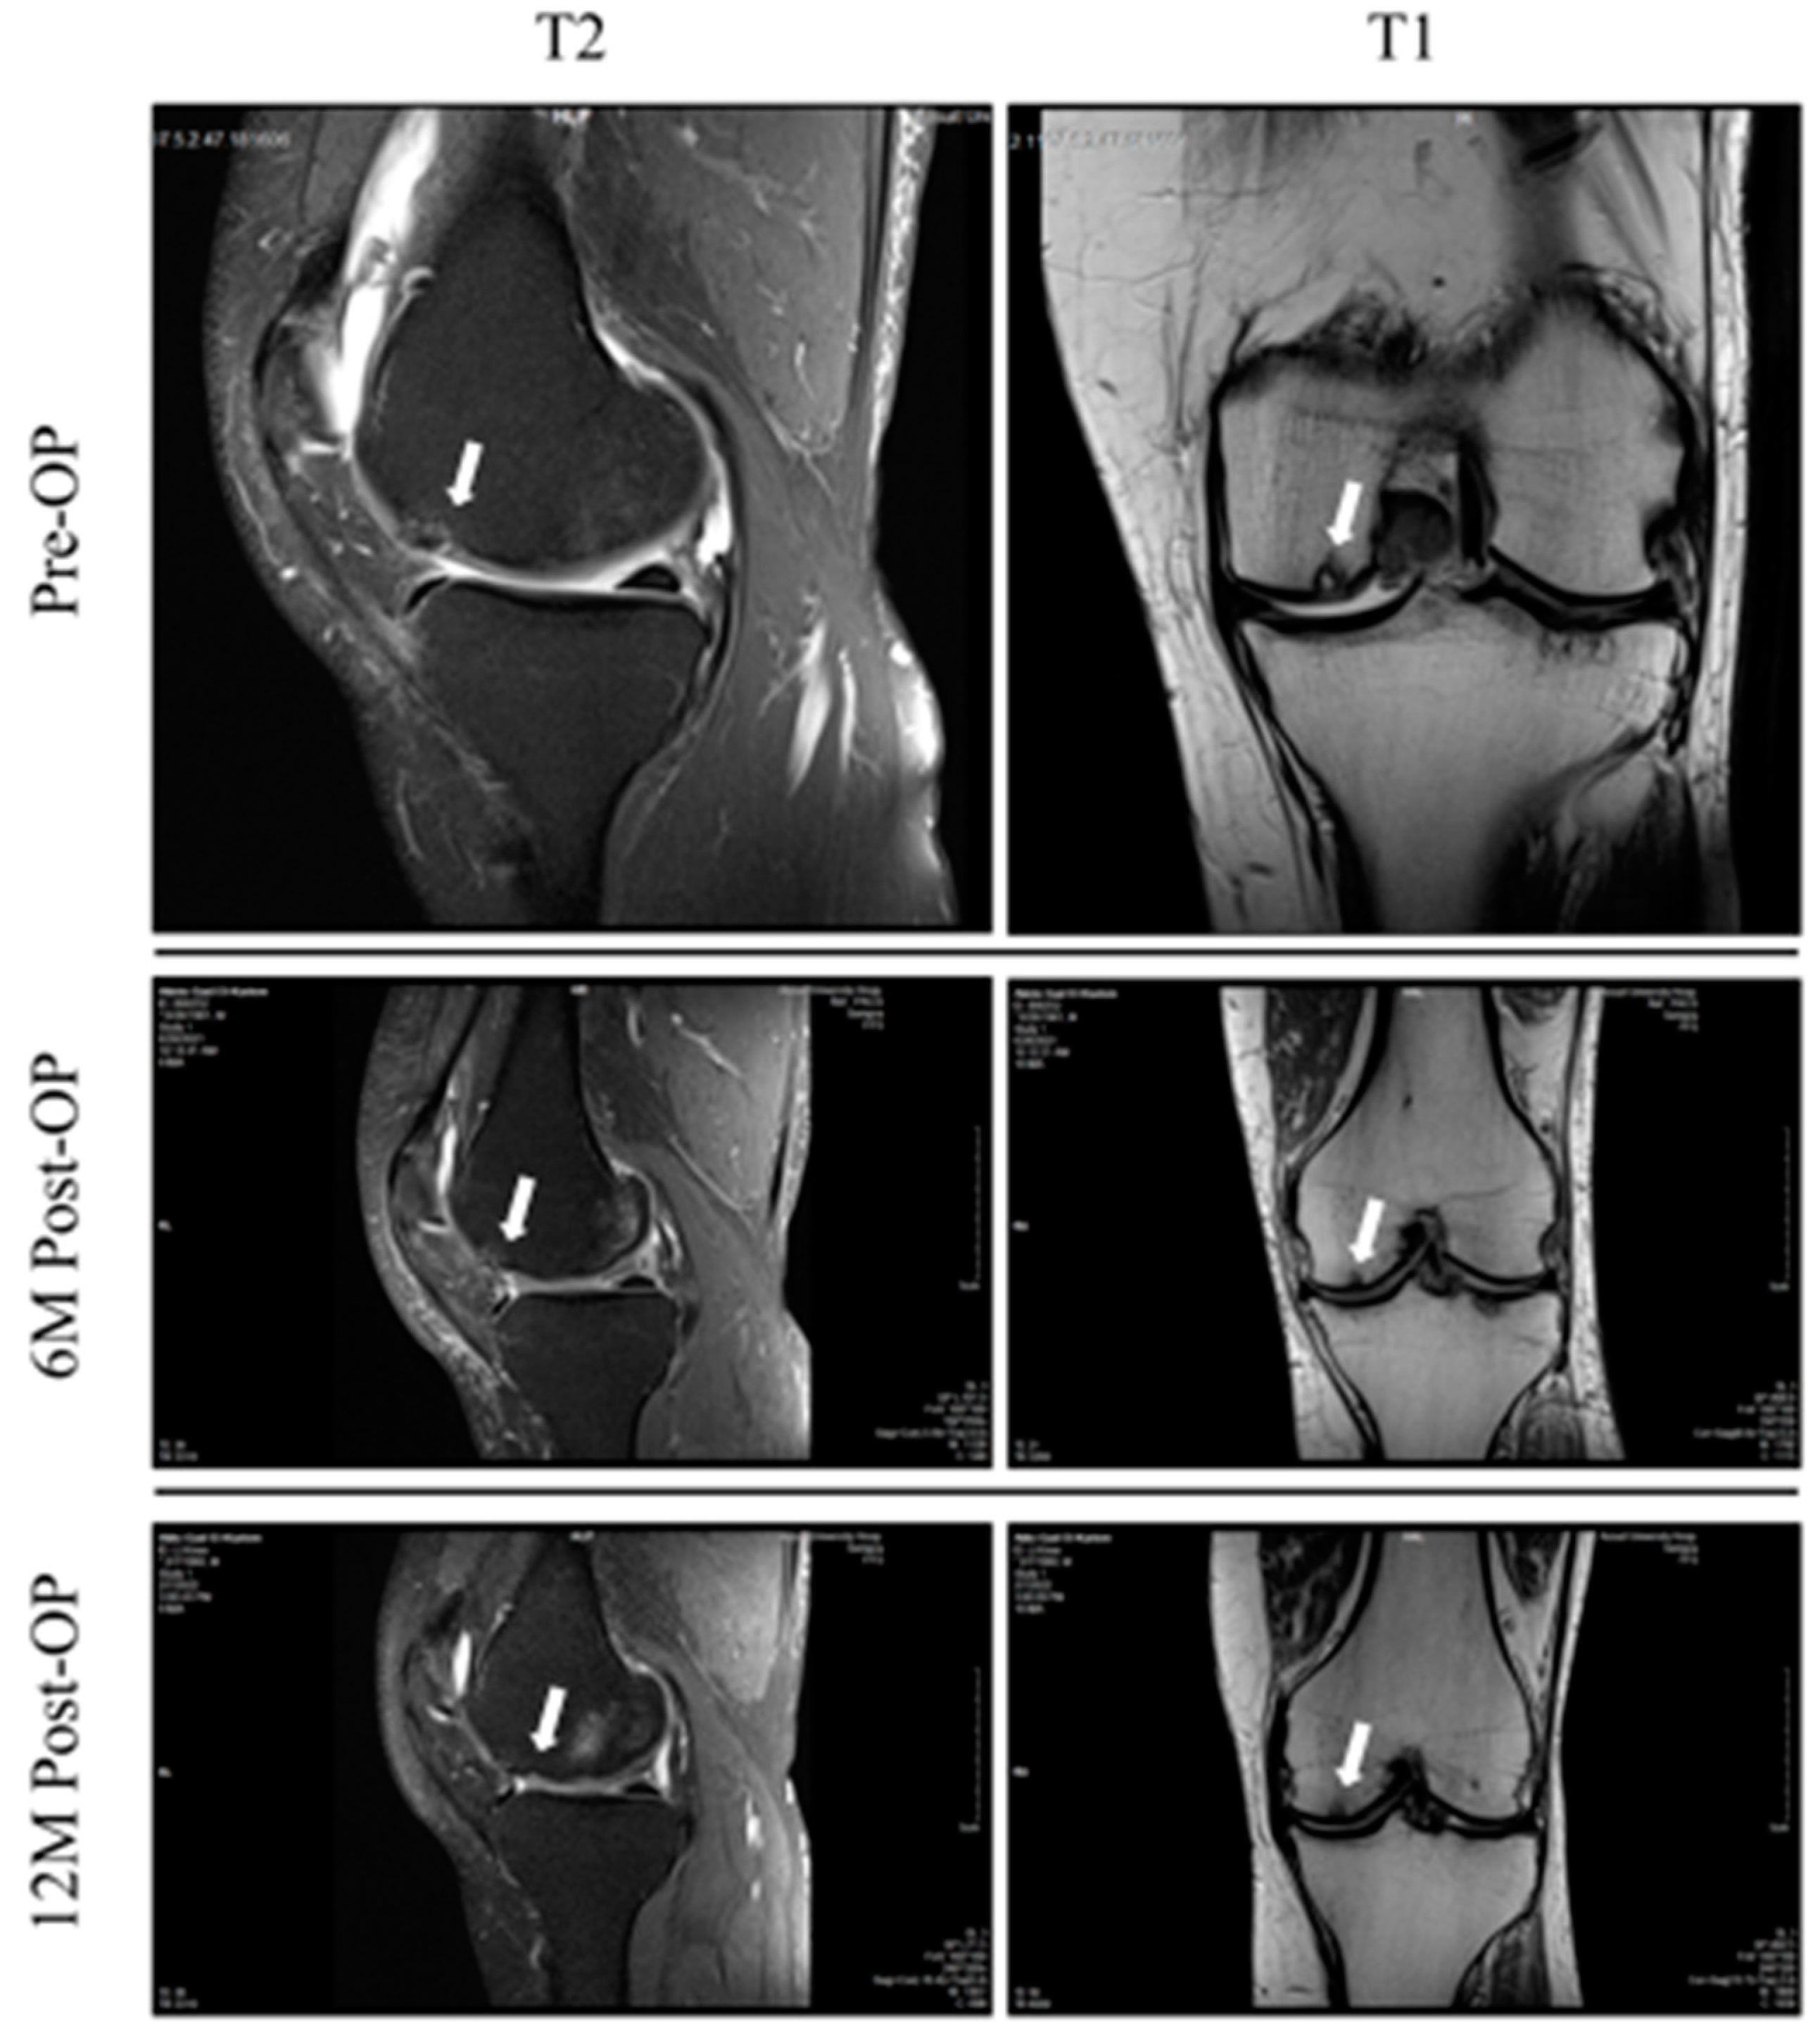

3.2.1. MRI Analysis and MOCART Score